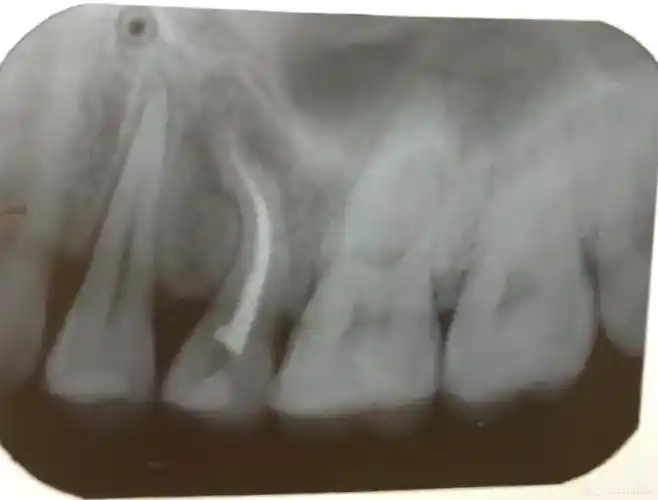

上颌第一磨牙远颊双根管1例

罕见上颌第一恒磨牙6根管的病例报告暨plex锉的根管治疗之路济南博士

上颌第一前磨牙4根管1例

上颌第一磨牙根管治疗流程